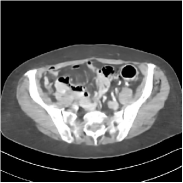

Fig. 2 shows a test example reconstructed using various methods.

Refer to caption

Figure 2: Reconstructions of slice 100 from patient L192 using various methods. The display window is [800 1200] HU.

We observe that PWLS-EP reduces the severe noise and streak artifacts observed in the low-dose FBP images, and the transform learning-based method PWLS-ULTRA further suppresses noise and reconstructs more details of the image such as the zoom-in areas. However, both methods have some blurry artifacts. The standalone FBPConvNet method heavily removes noise and streak artifacts, while introducing several artificial features (e.g., feature indicated by the arrow in the top-right box in Fig. 2). WavResNet denoises the image without introducing artifical features, but still retains some streaks around image boundaries and blurs some details (e.g., feature indicated by the arrow in the bottom-left box in Fig. 2). The state-of-the-art MAP-NN method performs slightly better than WavResNet in terms of suppressing streak artifacts, while it still loses some details as indicated in the zoomed regions. The competing plug-and-play unrolled method—ADMM-Net with WavResNet denoiser—outperforms the standalone WavResNet method, but still has some streak artifacts and blurred details. Compared to these methods, the proposed SUPER methods (SUPER-WRN-EP, SUPER-WRN-ULTRA, SUPER-FCN-EP, and SUPER-FCN-ULTRA) improve the reconstruction quality in terms of removing noise and artifacts, and recovering details more precisely. Two other example comparisons are included in the supplement (Fig. 10 and Fig. 11).